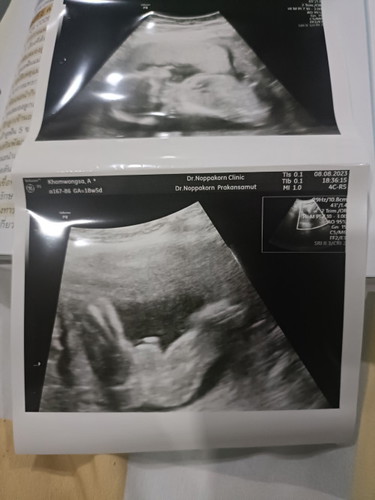

คุณแม่ช่วยดูหน่อยค่ะ

คุณแม่ช่วยดูหน่อยค่ะ ว่าเป็นเพศอะไรค่ะ

ชายค่ะ ไข่กลมดิ้กเลย

กำลังตั้งครรภ์